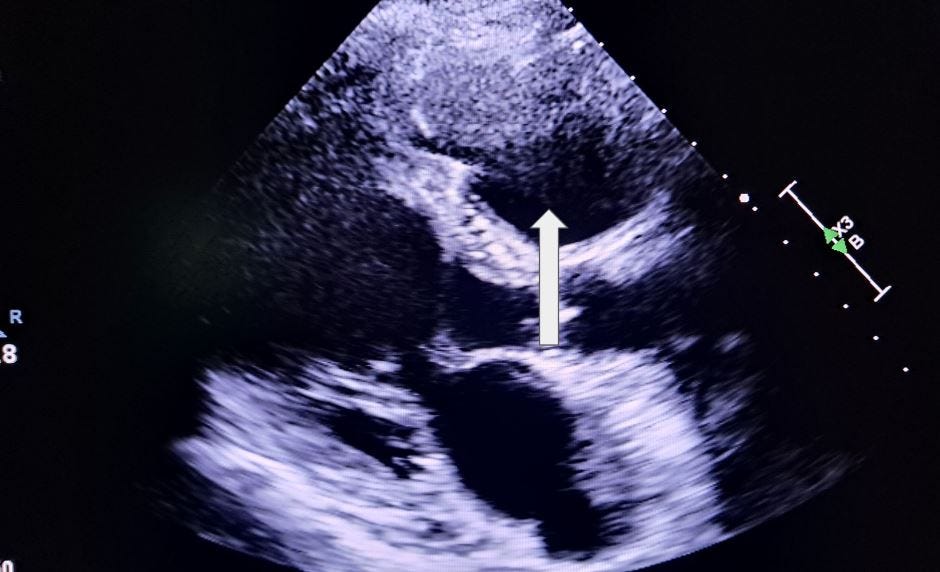

Which aortic cusp is the arrow indicating in this parasternal short axis image?

A. Anterior cusp

B. Non-Coronary cusp

C. Lateral cusp

D. Right coronary cusp